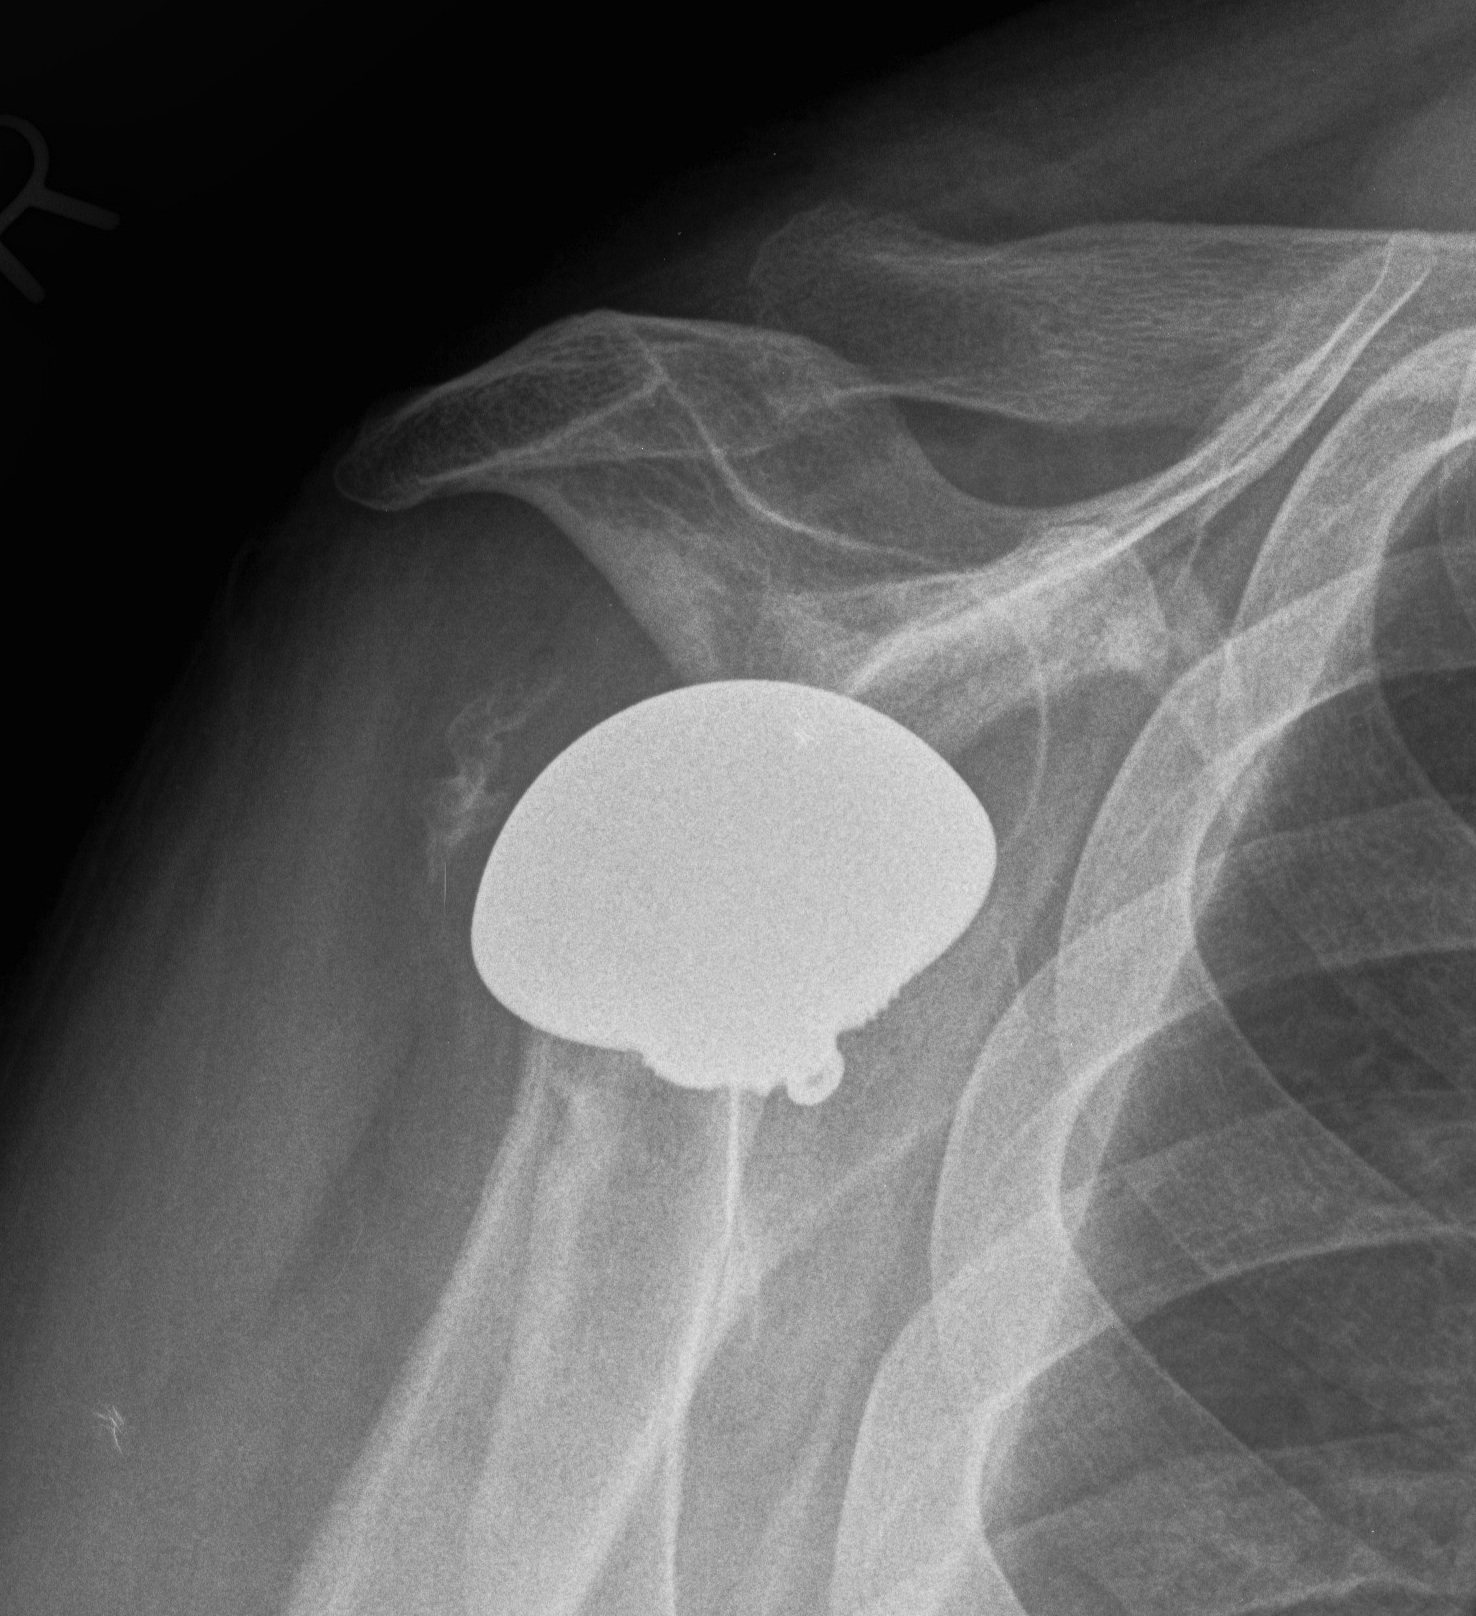

Reverse TSA +/- glenoid bone graft

Chronic locked with large Hill Sachs treated with rTSA + glenoid bone graft

Chronic locked with large Hill Sachs and normal glenoid treated with rTSA + glenoid bone graft